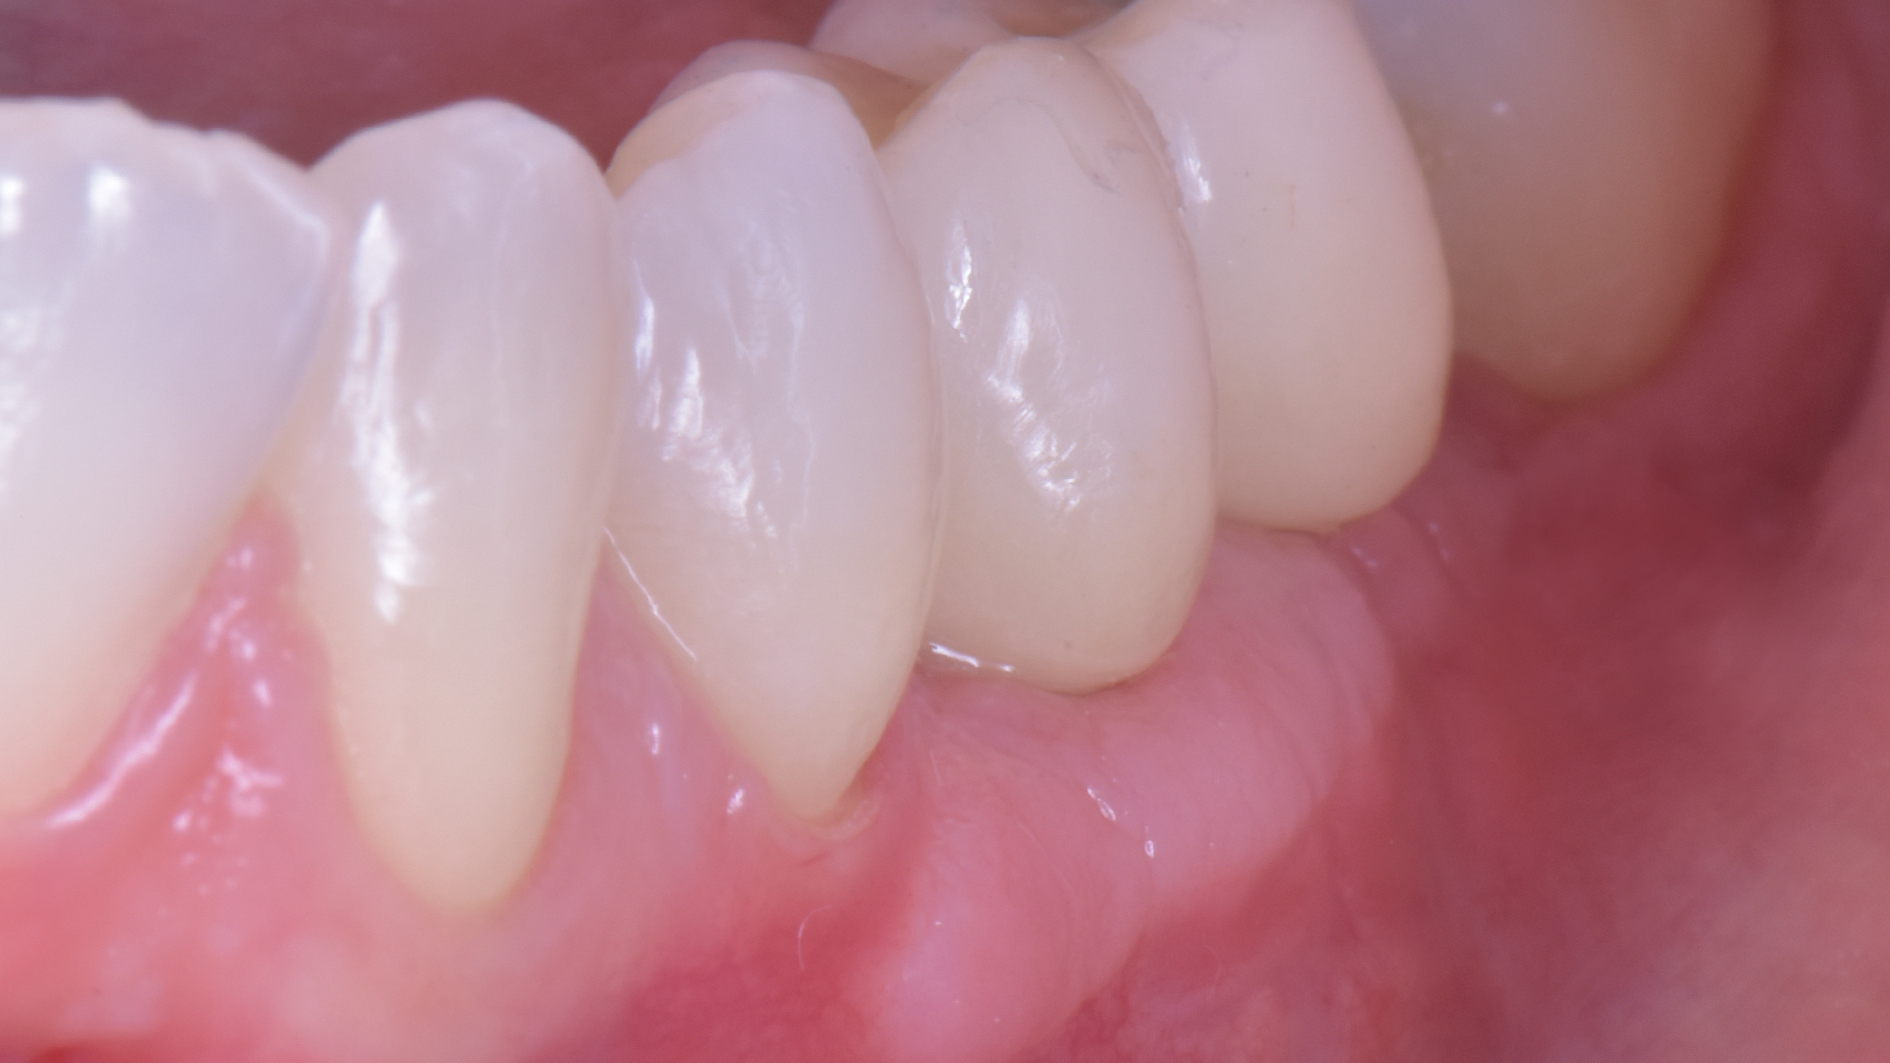

DSC_3896

Puoi buttare giù due viti e metterci sopra due denti facendo una cosa molto lontana dalla natura.

O puoi riabilitare la paziente adeguatamente: